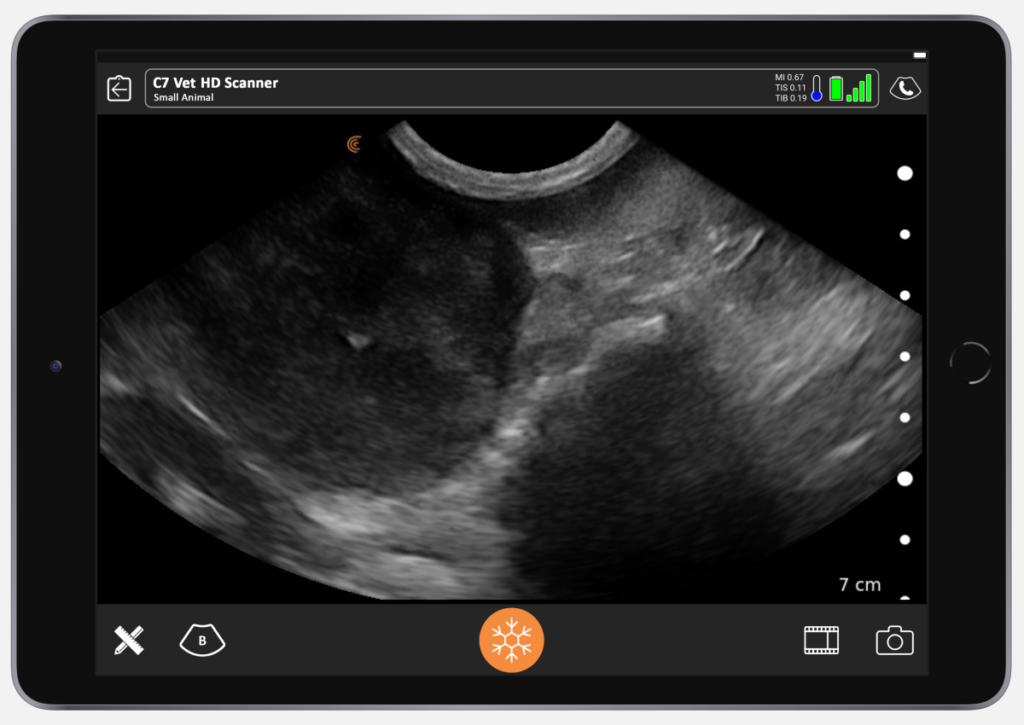

The ultrasound image below shows pathology we found in a beagle. The splenic head looks quite normal. But we see a mixed echogenicity mass.

There could be so many differentials. The diagnosis becomes more obvious if there’s also bleeding and then we are more worried that it is hemangiosarcoma. To confirm diagnosis, we need to get a sample. In this case, a sample unfortunately confirmed a hemangiosarcoma.